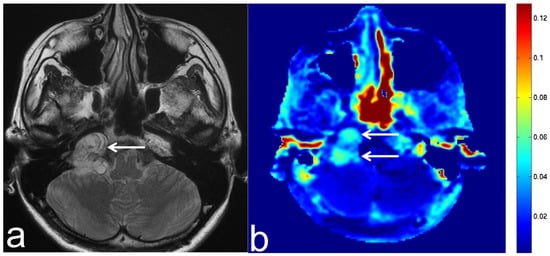

5.4. Malignant Lymphoma

5.5. Brain Metastasis